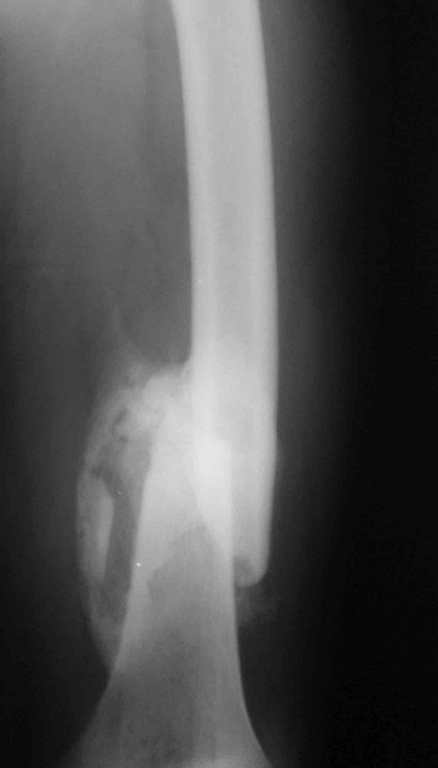

Иллюстрации к сообщению

Уважаемый Антон.Исходя из Вашего материального положения!! и наличия хорошего, грубого омозоления, равности длины конечностей и судя по снимкам не очень выраженной антекурвации, но выраженной контрактуры коленных суставов: чтоб не упустить время разработки суставов и активизировать больного, необходимо справа удалить стержень, рассверлить канал и произвести ЗИМО более толстым неблокир. стержнем т.к. на этом уровне можно получить устойчивый остеосинтез, после чего активизировать и дозированная, упорная ЛФК, а дальше после восстановления функции ,время покажеть.

Cyдя по представленным рентгенограммам оба бедра консолидированы. Необходима активная разработка движений в коленных суставах. Хотелось бы увидеть фотоснимки больного ( нижних конечностей спереди и сбоку). Если стержень мешает разработке движений то его надо удалить.

О происхождении такого запущенного случая- мой коллега работает экспертом ВТЭК и тянет в отделении и не такие казусы. Сегодня была сделана операция удален стержень из бедра и установлен стержневой аппарат из 2 опор, слева подвижности не наблюдалось, продолжается ЛФК. При необходимости позднее будет выполнена надмыщелковая корригирующая остеотомия. Спасибо всем за советы.